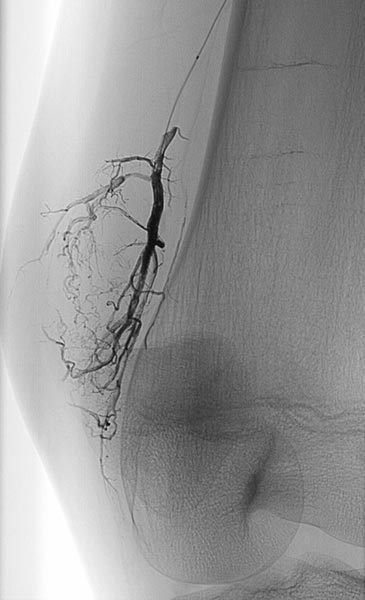

Digital subtraction angiography (DSA) in the early arterial phase shows a dilated feeding artery (so-called “feeder artery”), in this case a medial superior genicular artery. This artery is dilated over time due to chronic hyperperfusion with increased blood flow.

Digital subtraction angiography (DSA) in the arterial phase 2 s later shows some minor arteriovenous fistulas.

Digital subtraction angiography (DSA) in the interstitial and early venous phase again 4 s later shows no direct early venous outflow of the contrast agent but, instead, a pooling phenomenon. In an arteriovenous malformation, an immediate venous outflow would be seen because of multiple direct arteriovenous communications.

Super-selective catheterization of the feeding artery with a microcatheter again depicts multiple, fine arteriovenous fistulas, but not the immediate venous outflow as would be typical of an AVM. However, the visible arteriovenous fistulas are unusually prominent in this venous malformation.